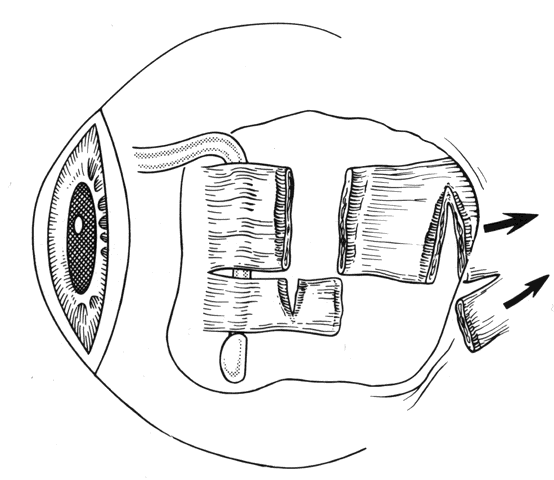

In some situations, a portion of a horizontal rectus may be left at the insertion site (Figs. 9 and 10). The muscle is usually split at the time of the initial procedure, and this can cause a shift of the distribution of force at the insertion and cause vertical misalignment. The pattern of the strabismus and the details of the previous surgery should provide clues to the problem and allow a logical approach for correcting the vertical deviation. Suspicions should be confirmed by careful dissection and exploration of the region of the muscle insertion. The importance of careful evaluation and elimination of mechanical restrictions cannot be overemphasized.4,10

Fig. 9. Residual exotropia or hypertropia can occur if a portion of the lateral rectus muscle is not recessed with the first procedure. To prevent this, care must be taken to incorporate all portions of the tendon when recessing an extraocular muscle.

Fig. 10. The pole test, or sweeping a Stevens muscle hook anterior to the insertion, will ensure that the entire tendon is on the Jameson muscle hook.